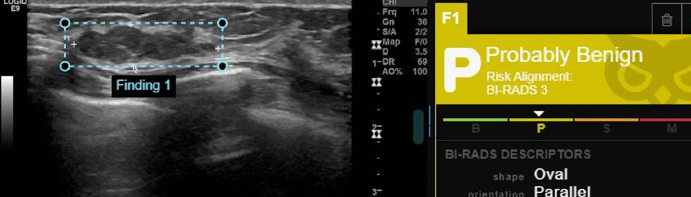

Materials and methods: Seventy suspicious breast mass lesions (53 malignant and 17 benign) from seventy women who underwent diagnostic breast US complemented with shear wave elastography, US-guided core needle biopsy and verified histopathology were enrolled. Two radiologists, one with 15 years of experience and the other with one year of experience, evaluated the images for breast imaging-reporting and data system (BI-RADS) scoring. The less-experienced radiologist re-evaluated the images with the guidance of a commercial AI system and the maximum elasticity from shear wave elastography. The BI-RADS scorings were processed to determine diagnostic performance and malignancy detections.

Results: The experienced reader demonstrated superior performance with an area under the curve (AUC) of 0.888 [95% confidence interval (CI): 0.793-0.983], indicating high diagnostic accuracy. In contrast, the Koios decision support (DS) system achieved an AUC of 0.693 (95% CI: 0.562-0.824). The less-experienced reader, guided by both Koios and elasticity, showed an AUC of 0.679 (95% CI: 0.534-0.823), while Koios alone resulted in an AUC of 0.655 (95% CI: 0.512-0.799). Without any guidance, the less-experienced reader exhibited the lowest performance, with an AUC of 0.512 (95% CI: 0.352-0.672). The experienced reader had a sensitivity of 98.1%, specificity of 58.8%, positive predictive value of 88.1%, negative predictive value of 90.9%, and overall accuracy of 88.6%. The Koios DS showed a sensitivity of 92.5%, specificity of 35.3%, and an accuracy of 78.6%. The less-experienced reader, when guided by both Koios and elasticity, achieved a sensitivity of 92.5%, specificity of 23.5%, and an accuracy of 75.7%. When guided by Koios alone, the less-experienced reader had a sensitivity of 90.6%, specificity of 17.6%, and an accuracy of 72.9%. Lastly, the less-experienced reader without any guidance showed a sensitivity of 84.9%, specificity of 17.6%, and an accuracy of 68.6%.

Conclusion: Diagnostic evaluation of the suspicious masses on breast US images largely depends on experience, with experienced readers showing good performances. AI-based guidance can help improve lower performances, and using the elasticity metric may further improve the performances of less experienced readers. This type of guidance may reduce unnecessary biopsies by increasing the detection rate for malignant lesions and deliver significant benefits for routine clinical practice in underserved areas where experienced readers may not be available.